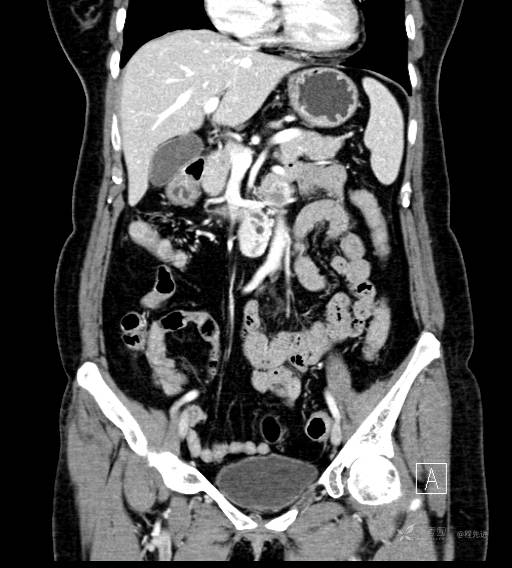

CT平扫

CT增强冠状位重建